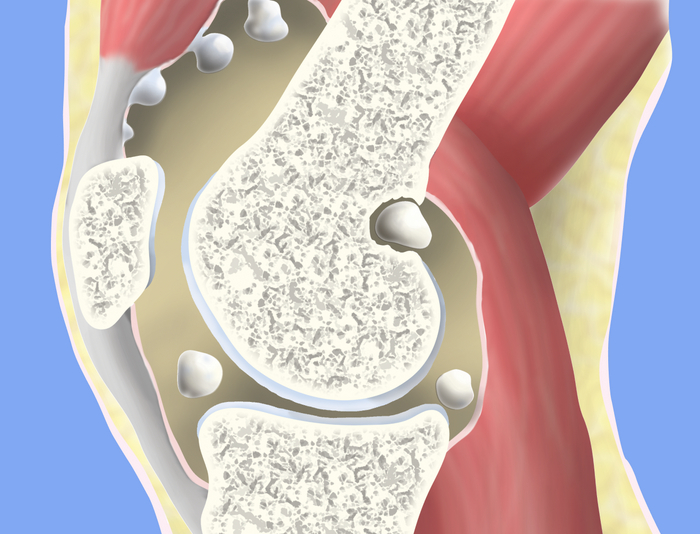

Хондроматоз – это патологическое изменение сустава, причиной которого становится перерождение синовиальной оболочки в хрящ. Это заболевание довольно редкое, может поражать любой сустав, но чаще всего страдает именно коленный сустав. Заболевание характерно для спортсменов и людей, подвергающихся регулярным тяжелым физическим нагрузкам, четкая причина возникновения неизвестна. Симптомы- боль, хруст и заклинивание сустава.

Описание: На Р-граммах правого к/с в 2х проекциях: Значительное сужение суставной щели в медиальных отделах до 1.6 мм, субхондральный склероз, краевые костные разрастания, заострение полюсов надколенника, уплотнение его внутренней поверхности ,по ходу внутренней поверхности синовиальной оболочки визуализируются единичные округлые хондроматозные тела №~7,размером от 5 мм до 25 мм в диаметре. Заключение: Хондроматоз правого коленного сустава. Гонартроз справа 3 ст. по Kellgren.Пателло-феморальный артроз.

Типичная локализация хондроматозных тел в к/с.

Лечение оперативное: артроскопическое удаление хондроматозных тел.